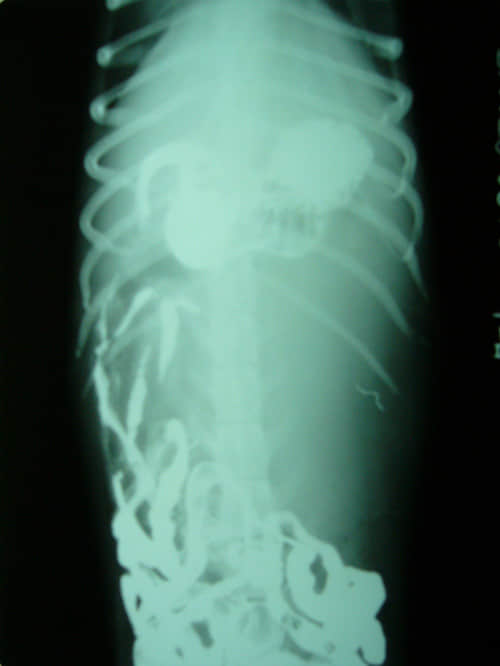

图3、造影后1.5小时正位片

图4、造影后1.5小时侧位片

图3、4可以看到,由于左侧腹腔肿块占位,将胃向前挤压,同时也把大部分肠管压迫到盆腔内,从正位片可以看到肿块占领整个腹腔左侧且越过脊椎侵袭到右侧。X光检查表明腹腔左侧有体积较大的肿块,根据肿块的位置和形态初步判断为肾肿大。